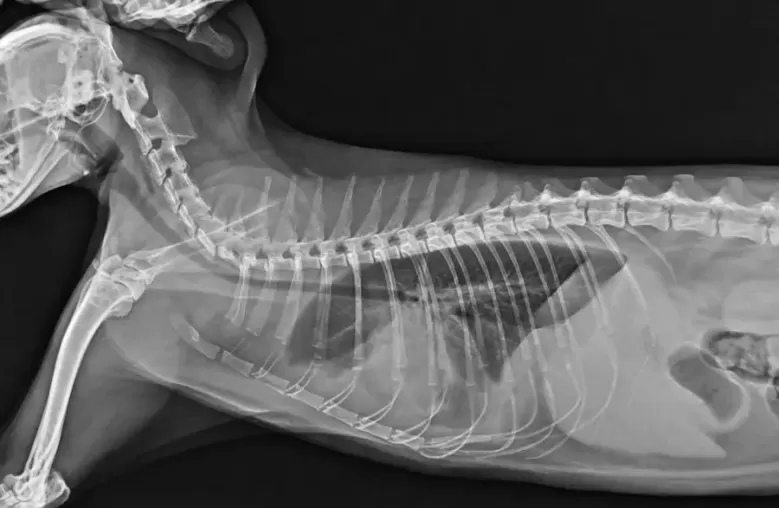

การตรวจโดยเครื่องเอกซเรย์ การถ่ายภาพรังสี

(Digital X-ray)

การถ่ายภาพช่องอกด้วยรังสีเอกซ์ใช้ในการตรวจวินิจฉัย ภาวะต่างๆ เกี่ยวกับทรวงอก อวัยวะภายใน และโครงสร้างข้างเคียง การถ่ายภาพรังสีทรวงอกเป็นการถ่ายภาพรังสีที่บ่อยที่สุดอย่างหนึ่ง และช่วยในการวินิจฉัยโรคและภาวะต่างๆ ได้หลายอย่างเช่นเดียวกับการตรวจอื่นๆ

โดยเฉพาะหากเกี่ยวข้องกับระบบทางเดินหายใจ ระบบหลอดเลือดและหัวใจ เช่นภาวะโรคหัวใจ ถุงลมโป่งพอง ภาวะน้ำท่วมปอด ปอดติดเชื้อ น้ำท่วมเยื่อหุ้มปอด มะเร็ง รวมถึงภาวะอุบัติเหตุอื่นๆที่อาจมีผลต่อซี่โครงหัก หรือภาวะเลือดออกในปอด ซึ่งจะเป็นวิธีการที่วินิจฉัยได้รวดเร็ว

ภาพ x-ray ระบบ Digital หัวใจแมว